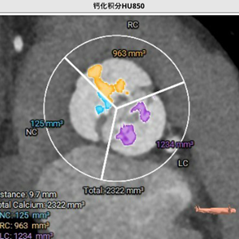

CT测量小结:

主动脉瓣为type -I 型二叶瓣,右无瓣叶嵴部融合伴有钙化并向窦部延伸16.0mm,瓣环平面可见钙化斑块向左室流出道延伸约12.3mm,瓣叶极重度钙化,中重度增厚;左冠窦较右无冠窦略偏大,右无冠窦基本等大;右冠脉开口高度可,左冠脉开口处可见瓣叶钙化斑块;心室大小可,室壁厚度可,中重度横位心;大血管走行自然,内径可,升主动脉扩张,主动脉弓部角度可,弓部、降主、腹主、左髂总动脉可见少-中量钙化斑块。

针对瓣膜型号选择,根据主动脉瓣环面积631.1mm2折算直径28.3mm,LVOT29.0mm,按照常规标准需选择29mm PrizValve。因患者瓣叶为极重度钙化(Hu850钙化积分2322),瓣膜型号可适当downsize,应能较好在瓣膜位置锚定,也有利于减少冠脉开口阻塞风险。